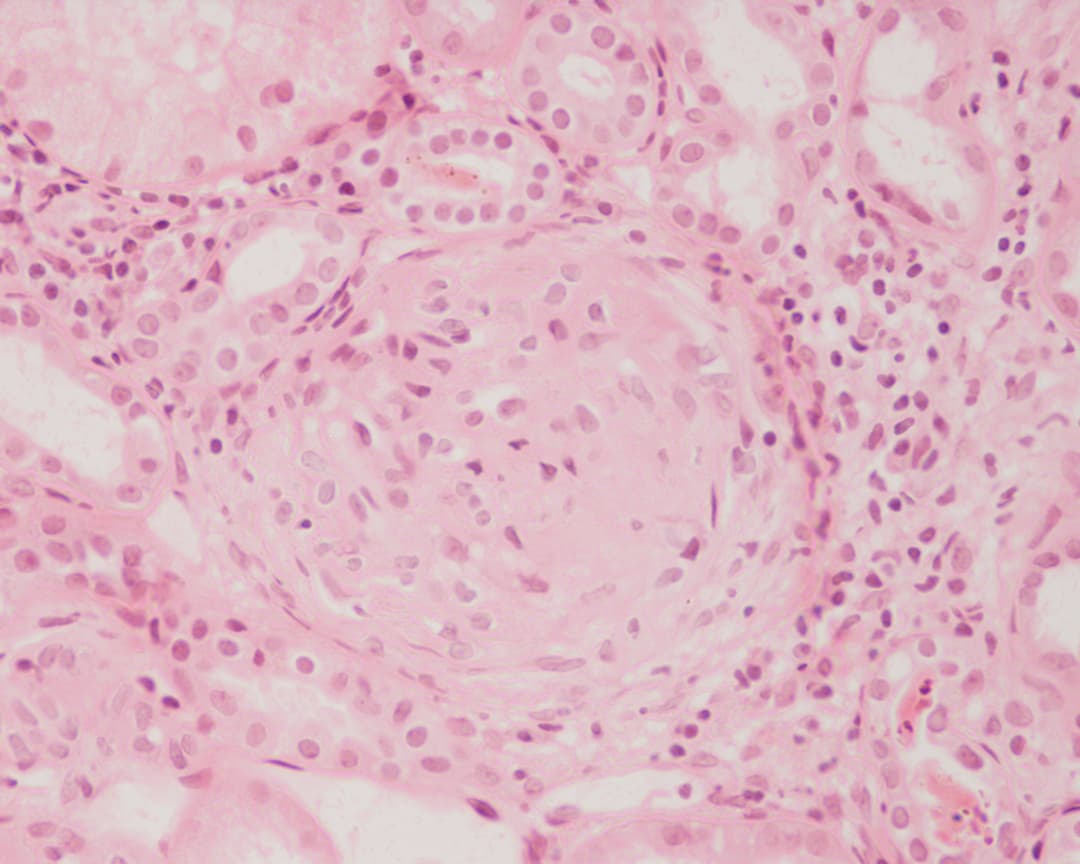

Glomerulonephritis (GN) is a term used to refer to several kidney diseases (usually affecting both kidneys). Many of the diseases are characterised by inflammation either of the glomeruli or of the small blood vessels in the kidneys, hence the name, but not all diseases necessarily have an inflammatory component. As it is not strictly a single disease, its presentation depends on the specific disease entity: it may present with isolated hematuria and/or proteinuria (blood or protein in the urine); or as a nephrotic syndrome, a nephritic syndrome, acute kidney injury, or chronic kidney disease. They are categorized into several different pathological patterns, which are broadly grouped into non-proliferative or proliferative types. Diagnosing the pattern of GN is important because the outcome and treatment differ in different types. Primary causes are intrinsic to the kidney. Secondary causes are associated with certain infections (bacterial, viral or parasitic pathogens), drugs, systemic disorders (SLE, vasculitis), or diabetes. Glomerulonephritis refers to an inflammation of the glomerulus, which is the unit involved in filtration in the kidney. This inflammation typically results in one or both of the nephrotic or nephritic syndromes. Nephrotic syndrome The nephrotic syndrome is characterised by the finding of edema in a person with increased protein in the urine and decreased protein in the blood, with increased fat in the blood. Inflammation that affects the cells surrounding the glomerulus, podocytes, increases the permeability to proteins, resulting in an increase in excreted proteins. When the amount of proteins excreted in the urine exceeds the liver's ability to compensate, fewer proteins are detected in the blood – in particular albumin, which makes up the majority of circulating proteins. With decreased proteins in the blood, there is a decrease in the oncotic pressure of the blood. This results in edema, as the oncotic pressure in tissue remains the same. Although decreased intravascular oncotic (i.e.